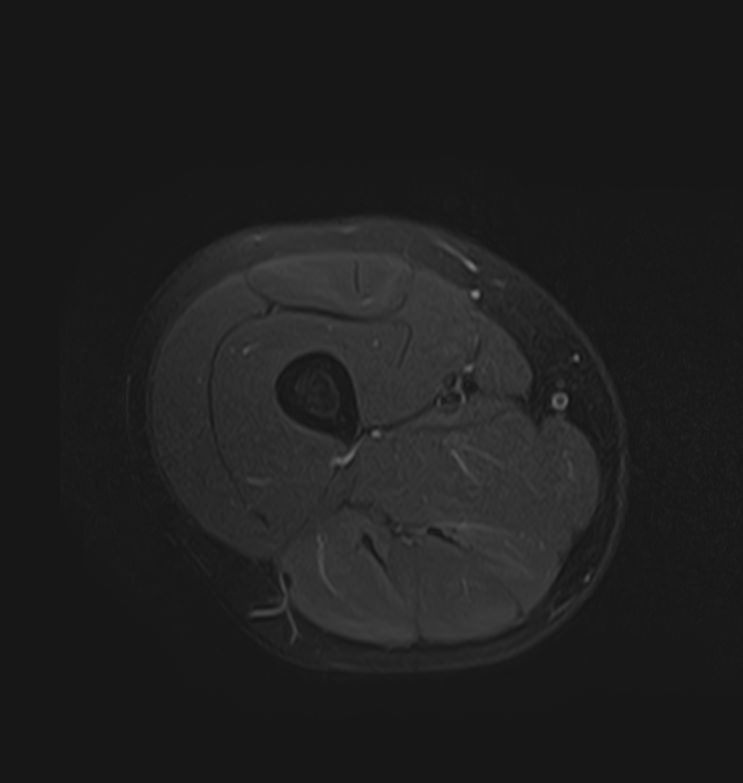

Магнитно-резонансная томография мягких тканей широко используется для детальной визуализации мягкотканных структур.

С помощью МРТ можно оценить состояние мышц, фасций, межфасциальных пространств, синовиальных оболочек, связок, сухожилий, сосудисто-нервных пучков, лимфоузлов и лимфатических протоков, надкостницы, кожи, подкожно-жировой клетчатки.

Метод магнитно-резонансной томографии по сравнению с другими исследованиями дает наиболее полную информацию о состоянии мягкотканных структур (по сравнению с УЗИ, традиционным рентгеновским исследованием и КТ). Кроме того, для повышения диагностической визуализации, например, при подозрении на развитие опухолевых процессов, дополнительно применяется контрастное усиление путем внутривенного введения гадолиниевого контрастного препарата.

- Доброкачественные и злокачественные новообразования кожи, подкожно-жировой клетчатки, мышечной ткани, нервов, суставных структур.